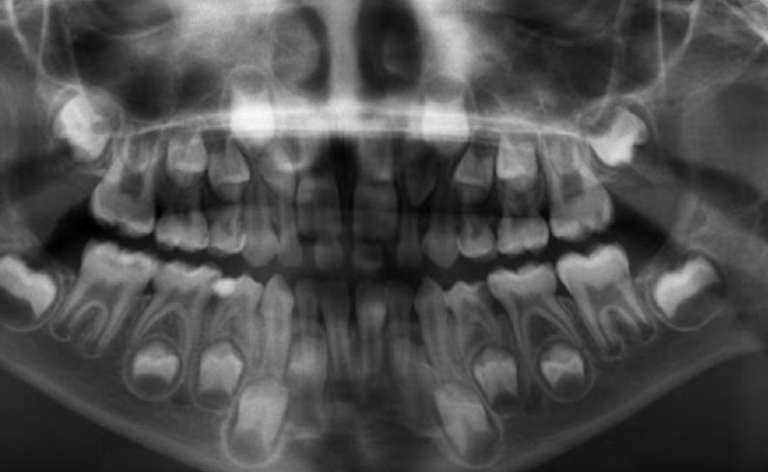

1.lower adult CI there? YES, so def 6-7

1. Upper Ad. Ci there? NO, so either 6-7 or under

Last molar crown not really formed so 6?

NOTE- THE 8’s - crown starts developing at 9 yo.